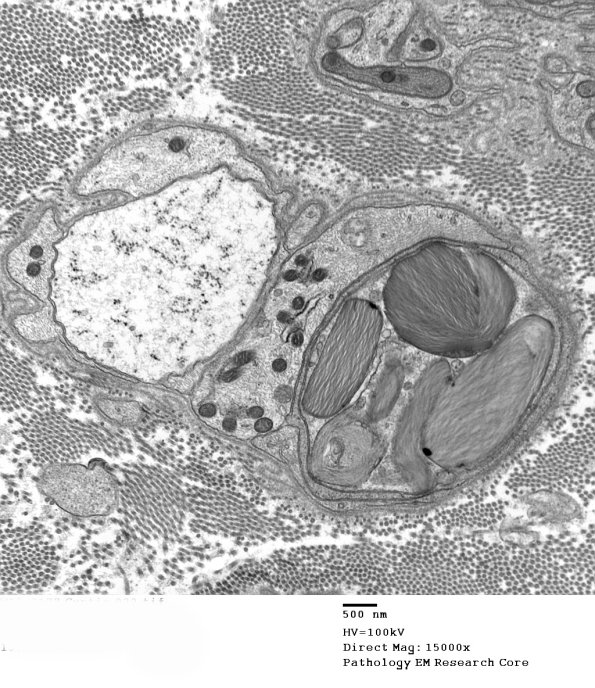

10A1,2 These Schwann cells, perhaps forming a rudimentary band of Büngner, are likely from a degenerated large myelinated axon since Schwann cells of unmyelinated axons usually do not contain Pi granules. (Electron micrographs)